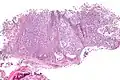

Micrograph of a myoepithelioma. H&E stain.

The myoepithelial cells may be spindled, plasmacytoid, eithelioid or clear. Tubules or epithelium are absent, or present in a small amount (<5%) by definition. Tumours with myoepithelial cells and a large amount of tubules are classified as pleomorphic adenomas (which must also contain the characteristic chondromyxoid stroma, which is normally absent in myoepithelioma).